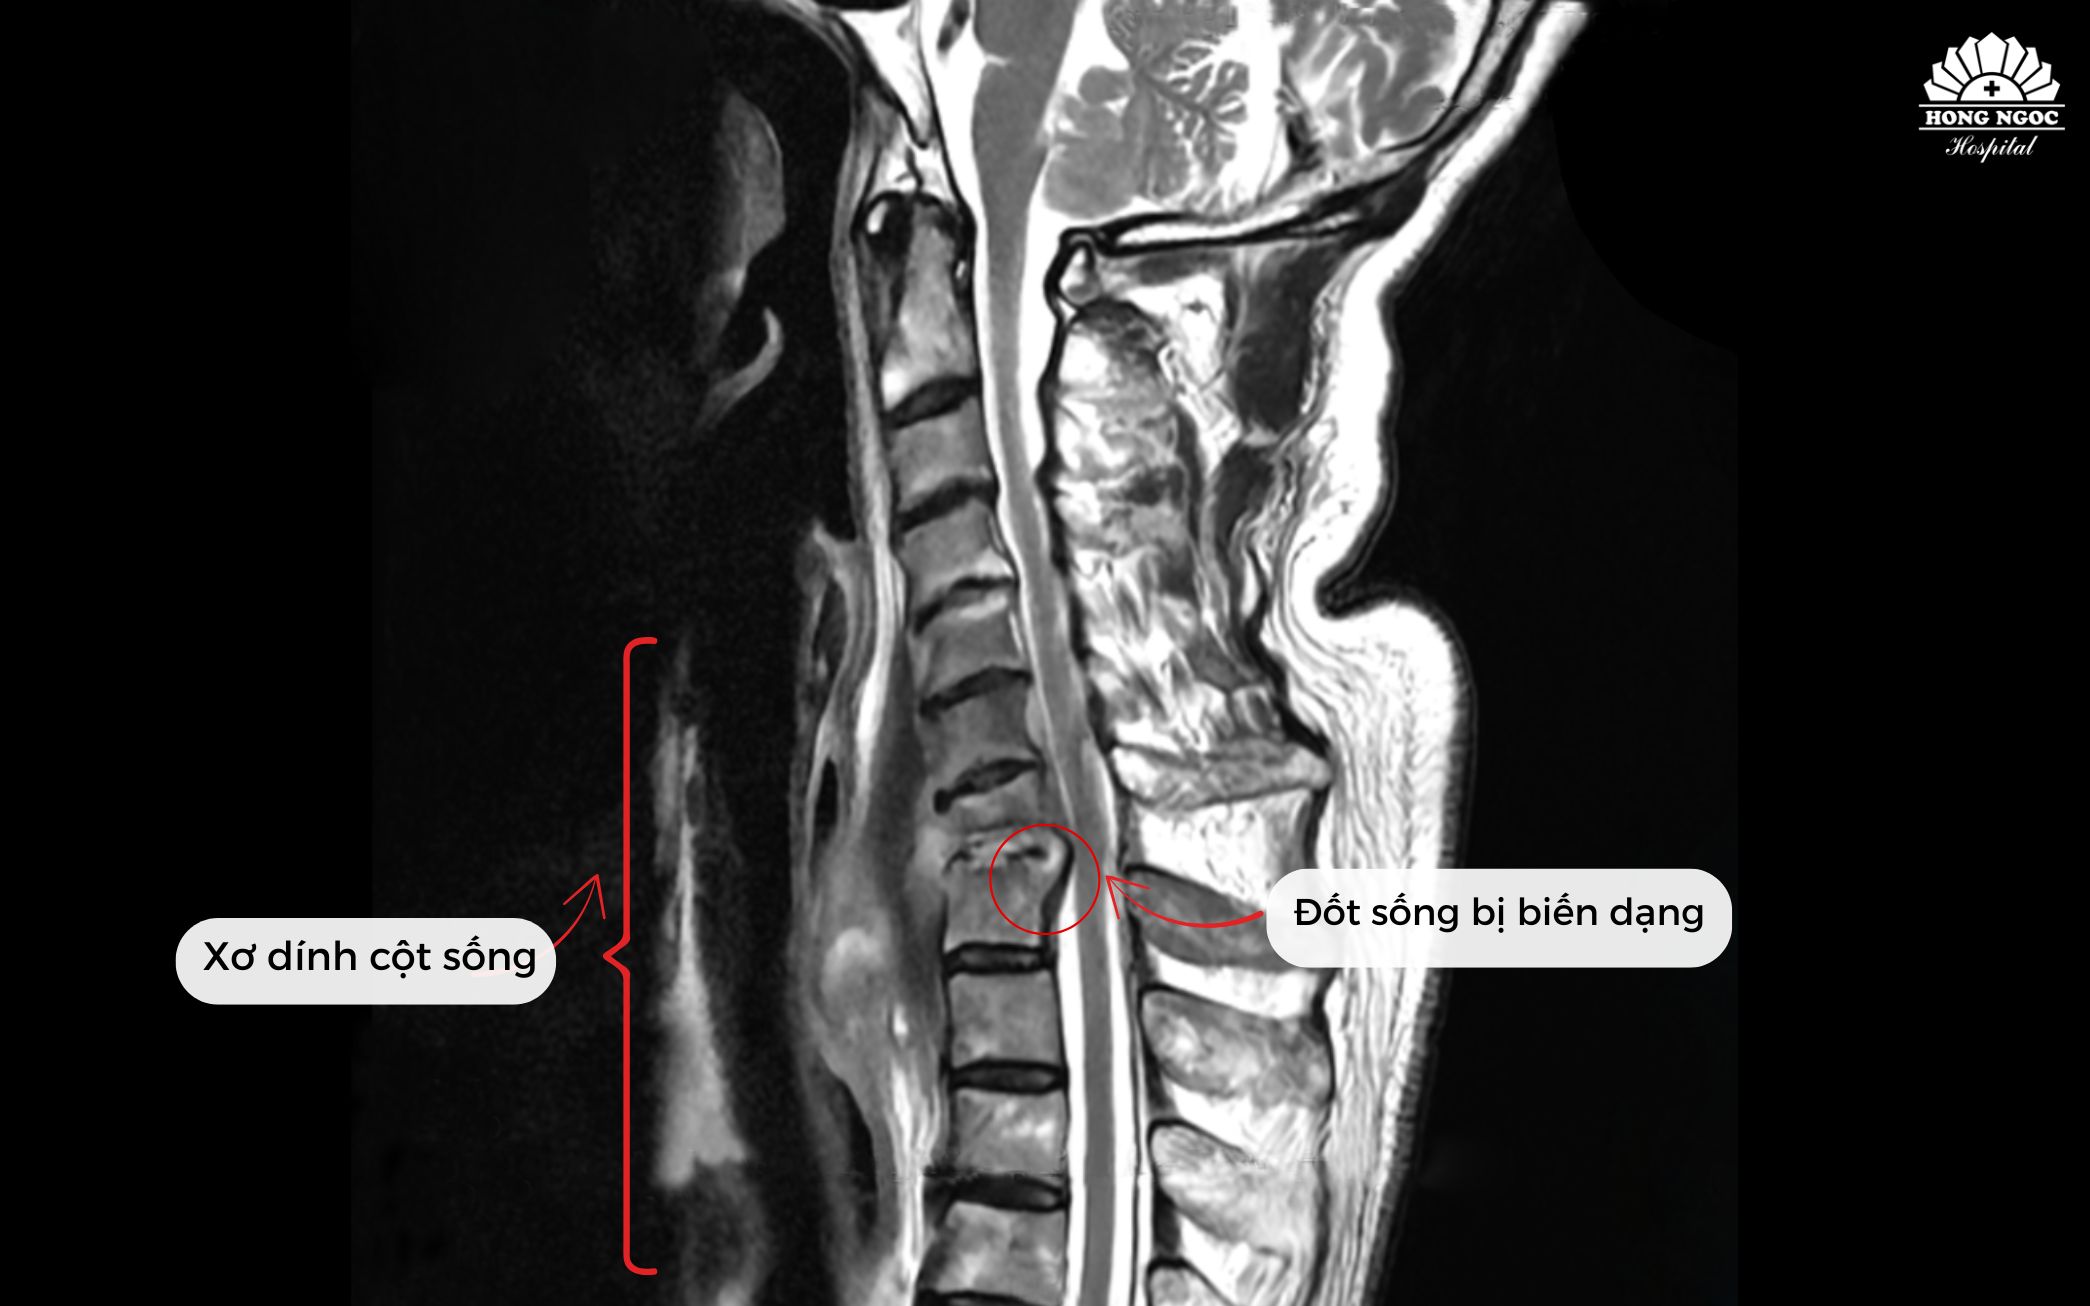

Theo PGS.TS.BS Hà Kim Trung (Chuyên gia phẫu thuật cột sống - Phó Giám đốc Y khoa BVĐK Hồng Ngọc - Phúc Trường Minh) phân tích: Qua kết quả chụp MRI cho thấy bệnh nhân bị nhiễm trùng cột sống cổ. Theo nhiều nghiên cứu y văn trên thế giới đây là tình trạng hiếm gặp, chỉ chiếm khoảng 2 - 7% trong tổng số các ca nhiễm trùng cơ xương khớp. Có thể xuất phát từ chấn thương, biến chứng sau phẫu thuật hoặc lây lan qua đường máu. Tình trạng viêm, áp xe phá hủy thân đốt sống và đĩa đệm C7/T1, tạo dải xơ co kéo khiến cổ bệnh nhân luôn trong tư thế gập, không thể xoay, ngửa. Nếu không phẫu thuật sớm, nguy cơ liệt vận động là rất cao.

Tình trạng xơ dính và đốt sống bị biến dạng trước phẫu thuật